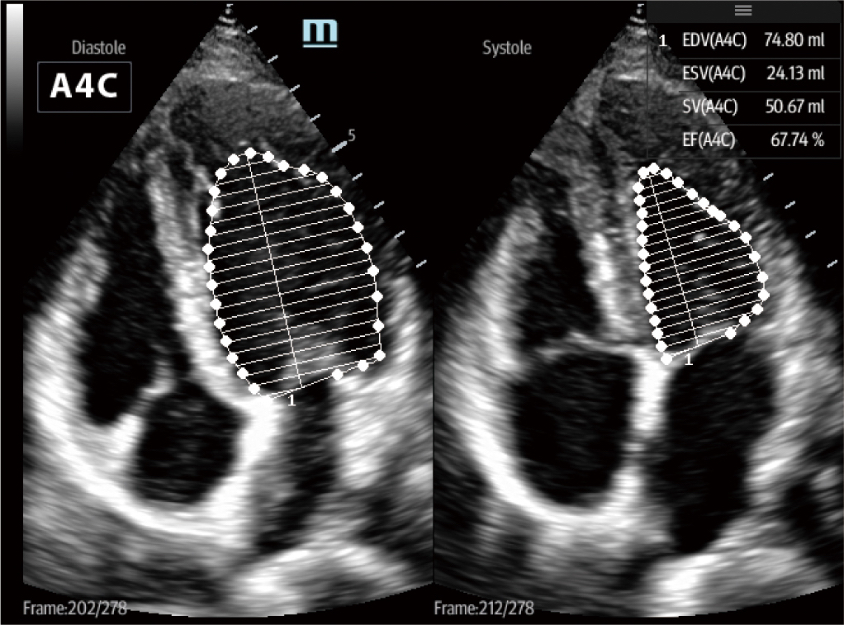

Después de la incubación de COVID-19, el virus invasivo causaría daño pulmonar, lo que eventualmente resultará en insuficiencia respiratoria y conducirá a la disfunción circulatoria y multiorgánica. El TE7 ACE equipado con funciones profesionales de evaluación pulmonar y prejustes de pulmón, como Smart VTI, Smart B-line, AutoEF, TDI etc., puede ayudar de manera eficiente al médico a controlar el perfil cardíaco y el estado de los líquidos durante el procedimiento terapéutico clínico.